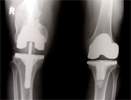

Healed but developed malunion and knee osteoarthritis, treated with intrarticular correction and knee replacement

Post

Op

2

nd

surgery : Good restoration alignment and pain relief

Progress

Patient had knee replacement done later for opposite knee also with good result

patient with good pain relief and knee motion